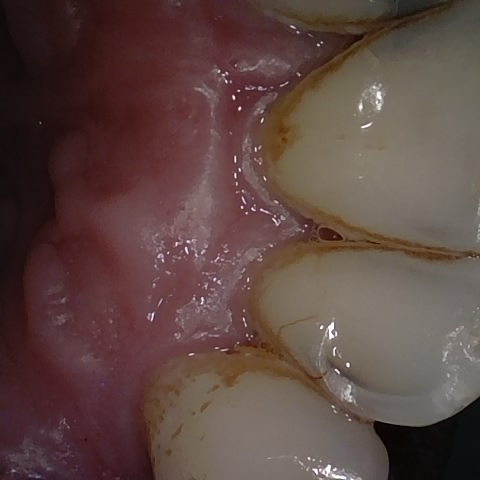

Annotated as "Good"